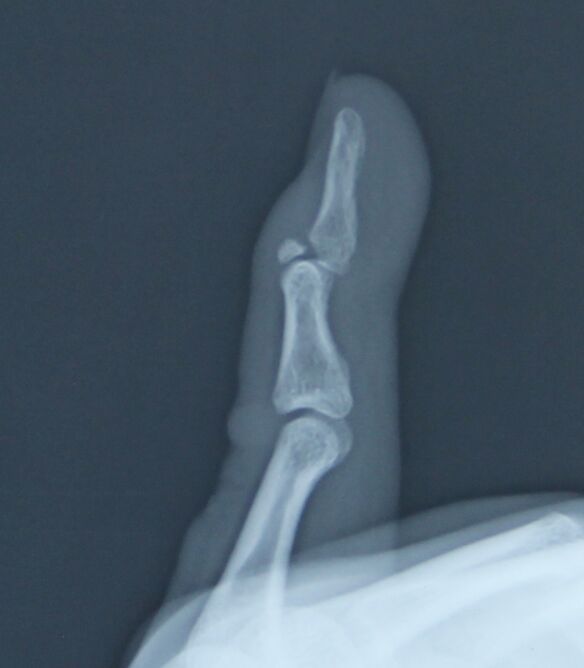

克氏针压扣法治疗骨性锤状指